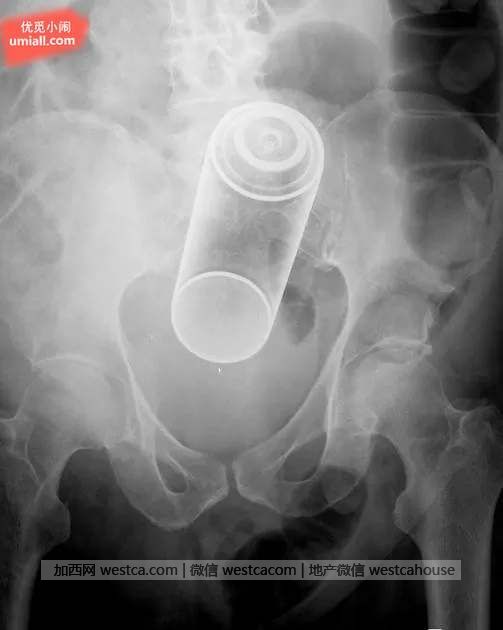

2. 喷气罐似乎很常莫名出现在人的体内…

我最想知道,不知道他的排气是否正常…